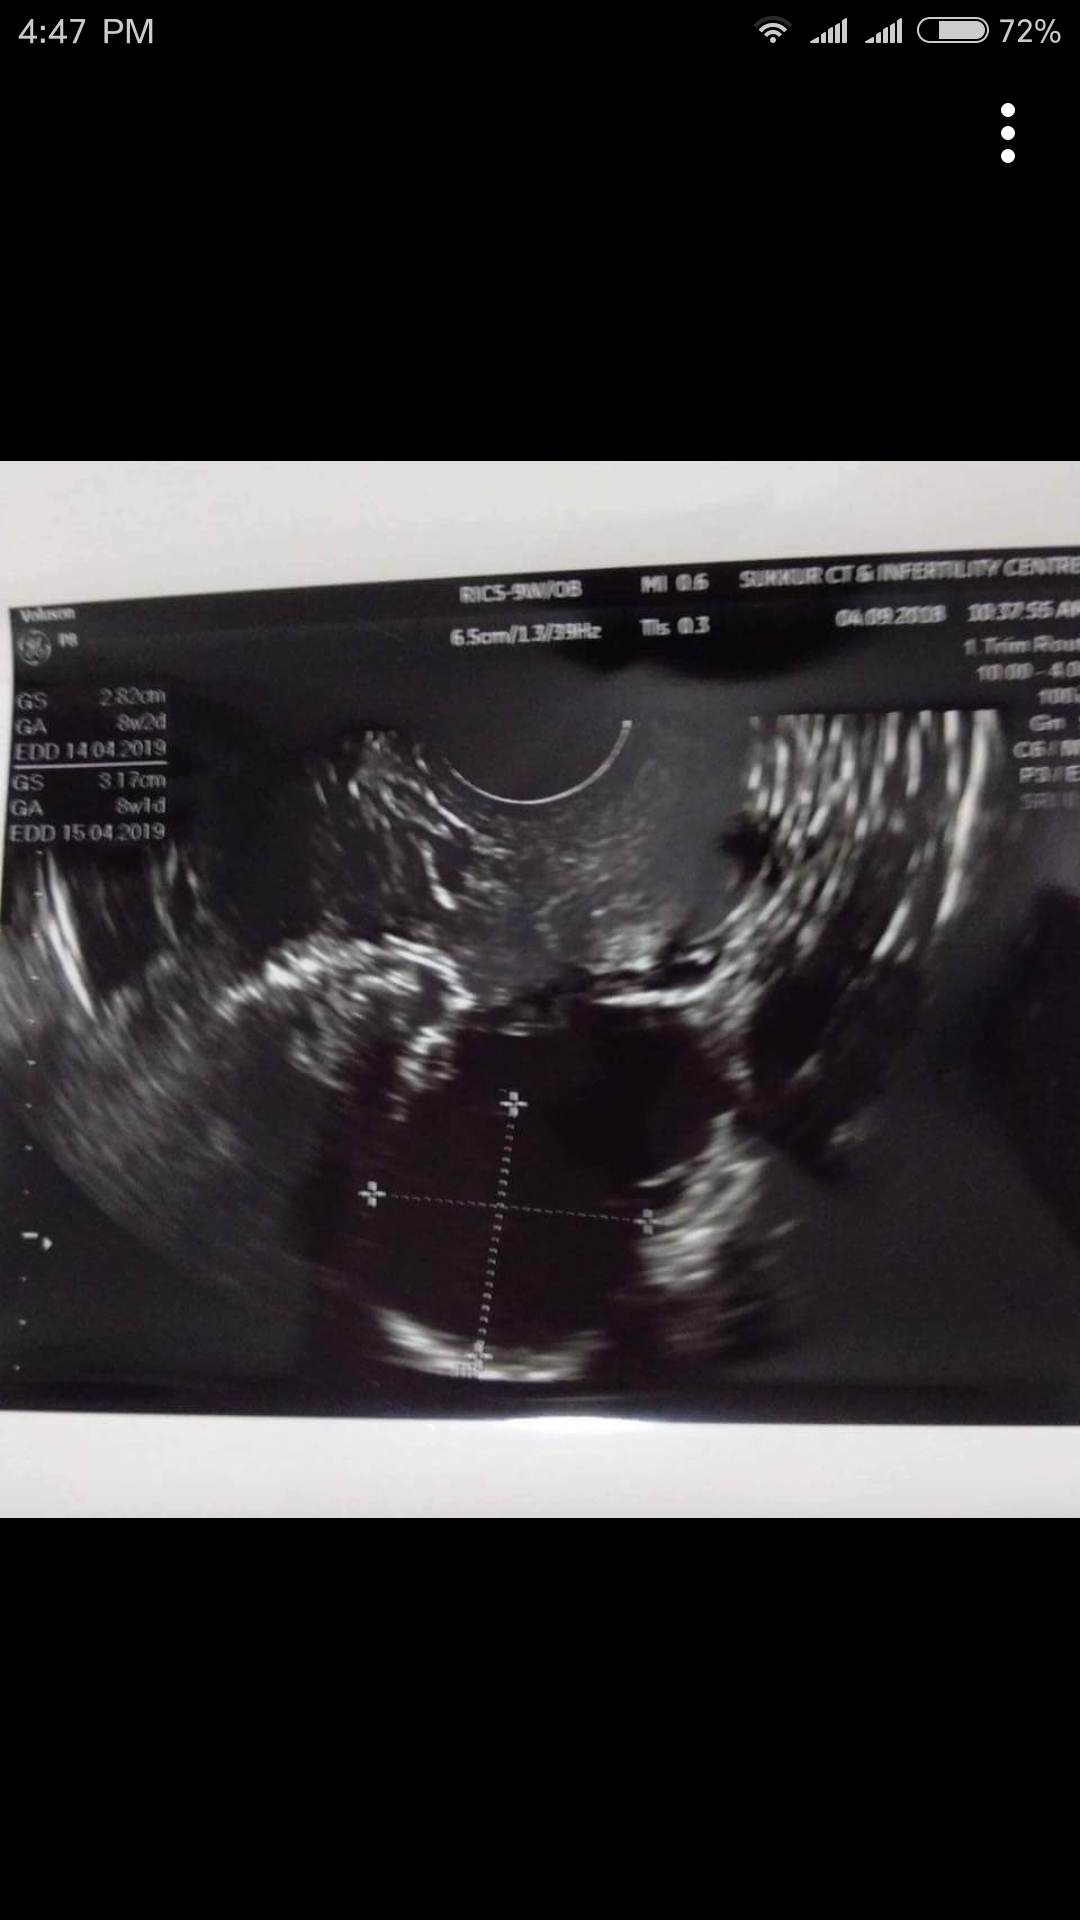

I was having green discharge and pain on right side of ovary during periods. 2 weeks ago I found out that I have a cyst in my right ovary. Dr. Gave me medications which included antibiotics as well. After a week I had TVS in which cyst size was reduced. I need to know will the cyst be dissolved on its own or should I continue taking treatment for cyst? I am trying to conceive since 6 months. Should I take treatment for conceiving or wait few more months?